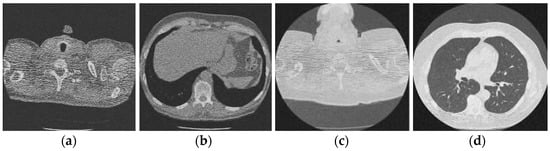

In this section, the experimental results of the proposed method over noisy CT images with their performance aspects are presented. All the experiments are performed on the standardized and simulated CT image data set with artificially introduced white Gaussian noise. Additionally, qualitative, quantitative, and graphical analysis is done to provide evidence for the efficacy of the proposed method. The reference CT image dataset is shown in Figure 2. The CT images are of [512 × 512] resolution size, which is used for consistency. This framework can work with dynamic image size, and performance commensurate to the available hardware. The image shown in Figure 2d refers to grayscale using built-in MATLAB functions before use.

Figure 2.

Online access database of original CT images [49]; (a) Reference CT1 image; (b) Reference CT2 image; (c) Reference CT3 image; (d) Reference CT4 image.